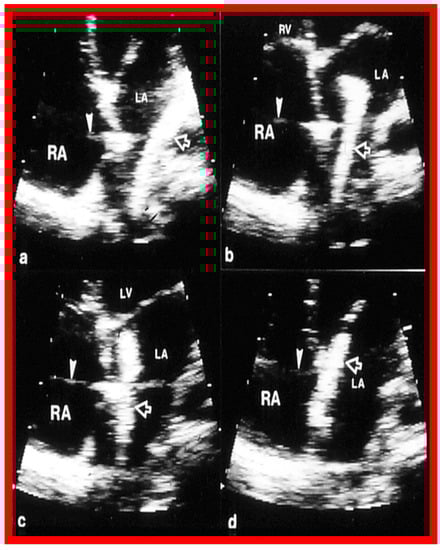

2. Diagnosis

6. TEE and ICE

9. Follow-Up after Device Occlusion

9.2. Device Position